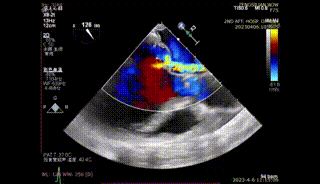

图1-4. 术前在交界、左室长轴切面及3D视角下可见大量二尖瓣反流,反流区宽,MultiVue下可见P2-P3脱垂